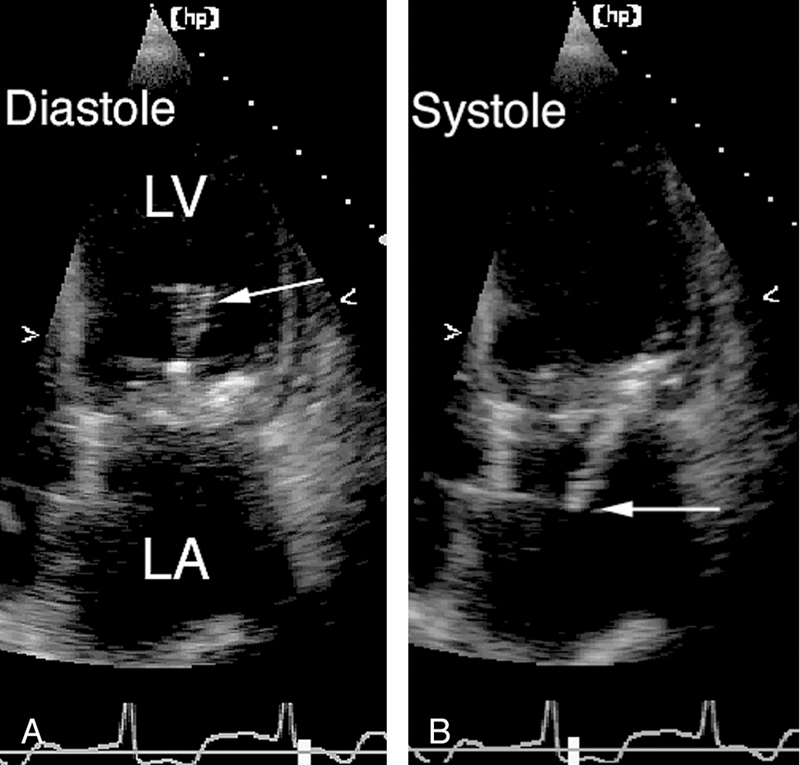

فحوصات تشخيصية لبعض امراض القلب والشرايين التاجية